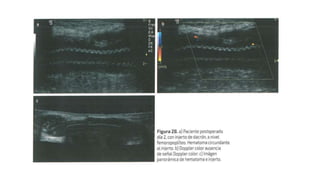

Evaluación para ladeterminación de trombosis del bypass